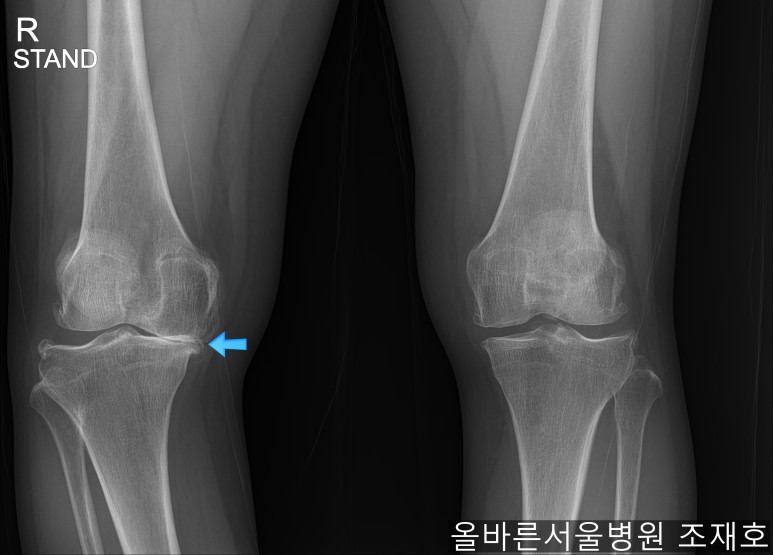

仅通过放射线片子观察到:右膝由于炎症严重,内侧胫骨及股骨已接触在一起,向内测严重变形。

左膝虽然也观察到了炎症,但远不如右膝严重。

如果通过X光片也观察到相同的病症,可以判断内侧关节的软骨大部分都损伤了。